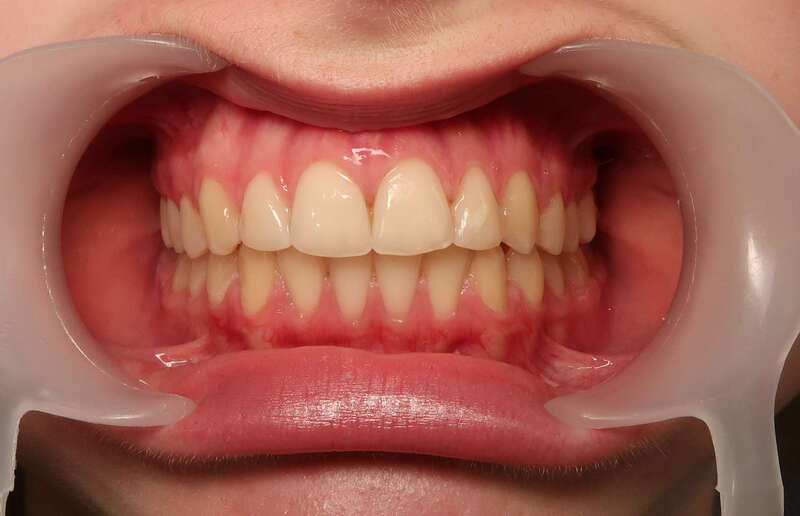

Cas n°2 traité par aligneurs - adolescent

Ce cas d'une adolescente illustre la puissance des aligneurs dans la correction d'une Classe II sévère sans extraction. La stratégie a reposé sur une distalisation séquentielle de l'arcade supérieure, soutenue par une coopération soutenue du port d'élastiques intermaxillaires.

Cette approche a permis d'annuler un surplomb incisif (overjet) important tout en réhabilitant une occlusion de Classe I stable. L'absence d'extraction a été déterminante pour préserver l'harmonie du profil, évitant le creusement du visage souvent lié aux traitements soustractifs classiques.

• Conservation dentaire : Alignement total sans perte de prémolaires.

• Fonctionnalité : Engrènement parfait et stable.

• Esthétique faciale : Soutien labial optimal et sourire élargi.

C'est une démonstration claire de l'orthodontie moderne : efficace, esthétique et respectueuse de l'anatomie naturelle.